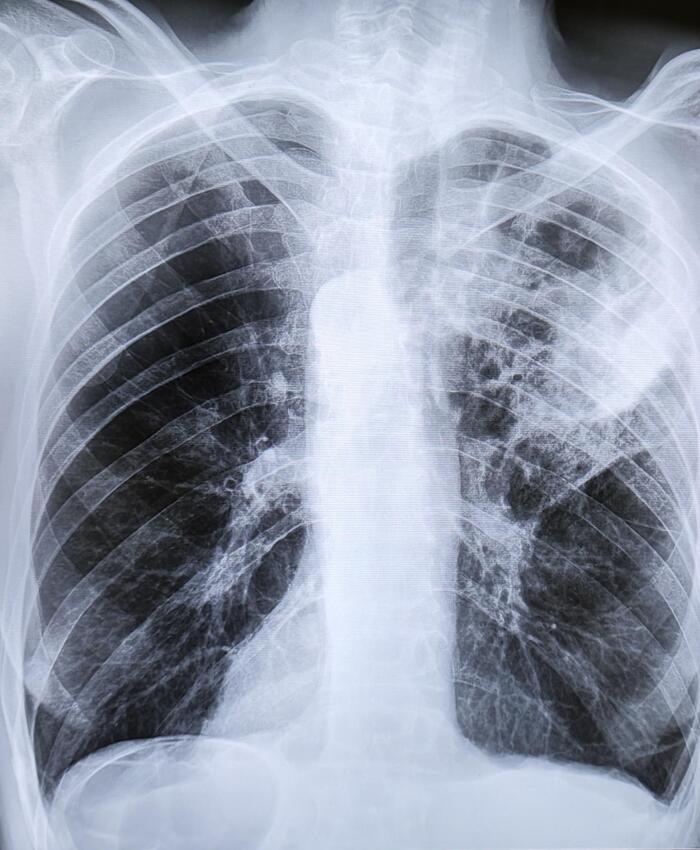

Двустороннее ассиметричное скопление жидкости плотностью +10-20 HU,с максимальной толщиной выпота справа -42мм,слева-16мм(ориентировочный объем жидкости справа-530мл,слева-157мл).

Заключение: Двусторонний гидроторакс, средний по объему-справа, малый-слева.